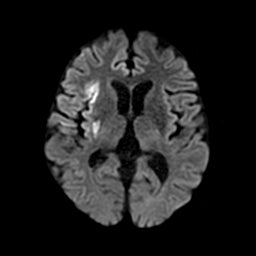

2. 周囲及び前後のスライスと比較して低吸収の領域及び、頭蓋内で前後のスライス・同一スライス内左右で比較して組織構造や組織境界の不明瞭化が見られる領域の抽出・表示

2-1. 低吸収領域の検出・表示例(下)

頭部CT検査において、周囲に比べ白く映る部分(高吸収領域)が見られる場合には、脳出血が疑われます。脳出血は高血圧・脳腫瘍・脳血管の異常などが要因となり、脳の動脈が破れて脳内部に出血した状態を指します。一方、周囲に比べ黒く映る部分(低吸収領域)が見られる場合には、脳梗塞が疑われます。脳梗塞は、脳内の血管が詰まるなどにより血液の流入が止まり、脳に酸素や栄養が行き渡らなくなる状態です。また、急性期の脳梗塞では、頭部CT検査において、灰白質と白質の境界が消失するなどの所見(ECS=early CT sign)が見られ(2)、こうした所見を見落とさずに治療につなげることが肝要です。